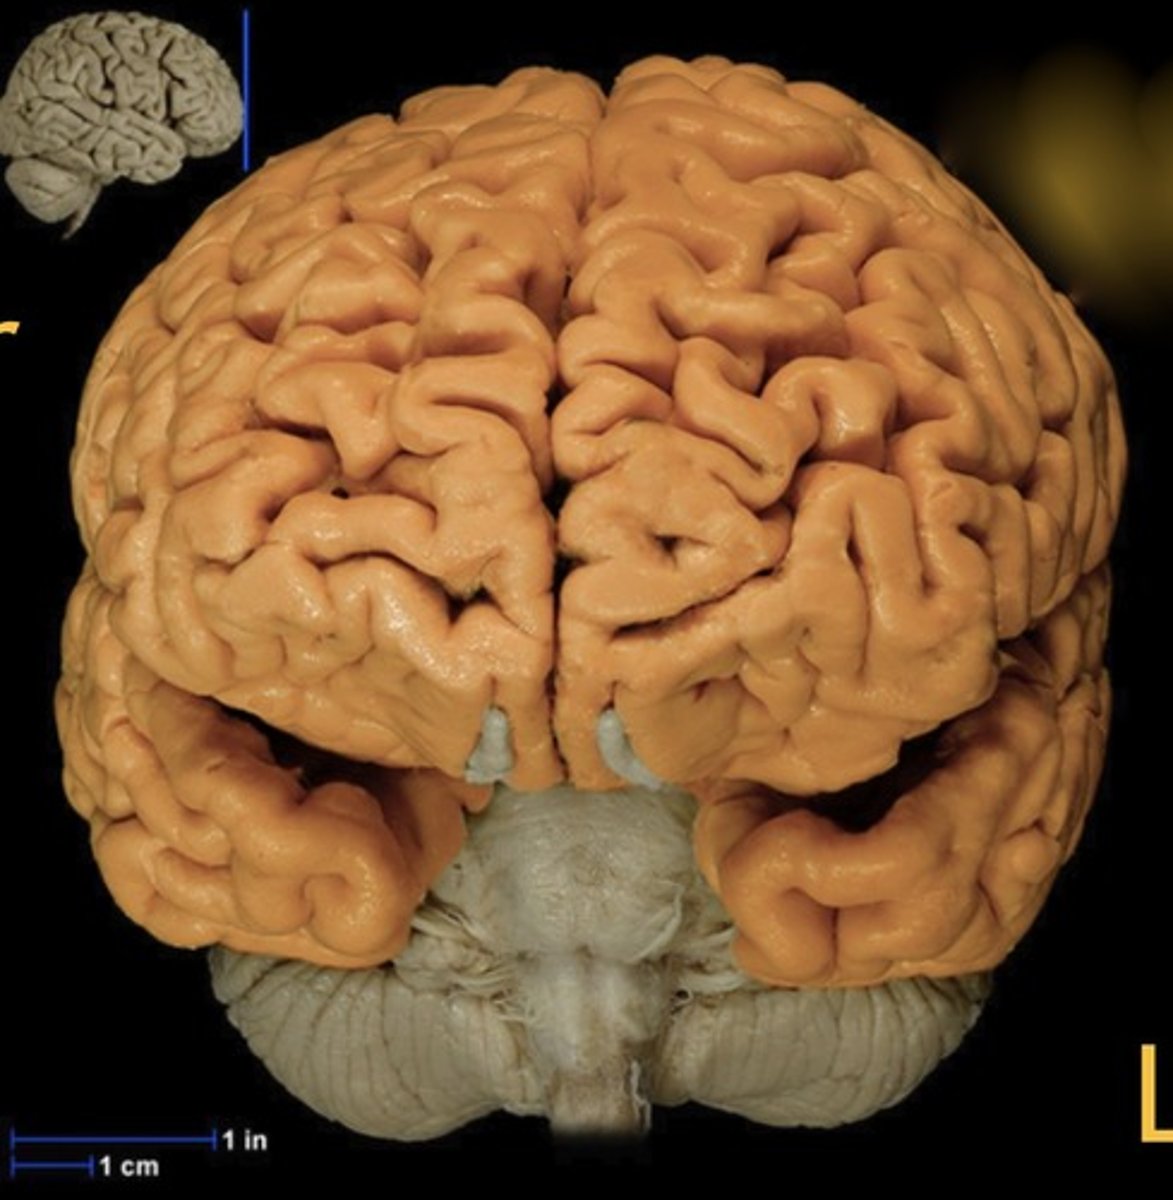

Cerebrum

Name this structure

Longitudinal fissure

Name this structure

Brainstem

Name this structure

Cerebellum

Name this structure